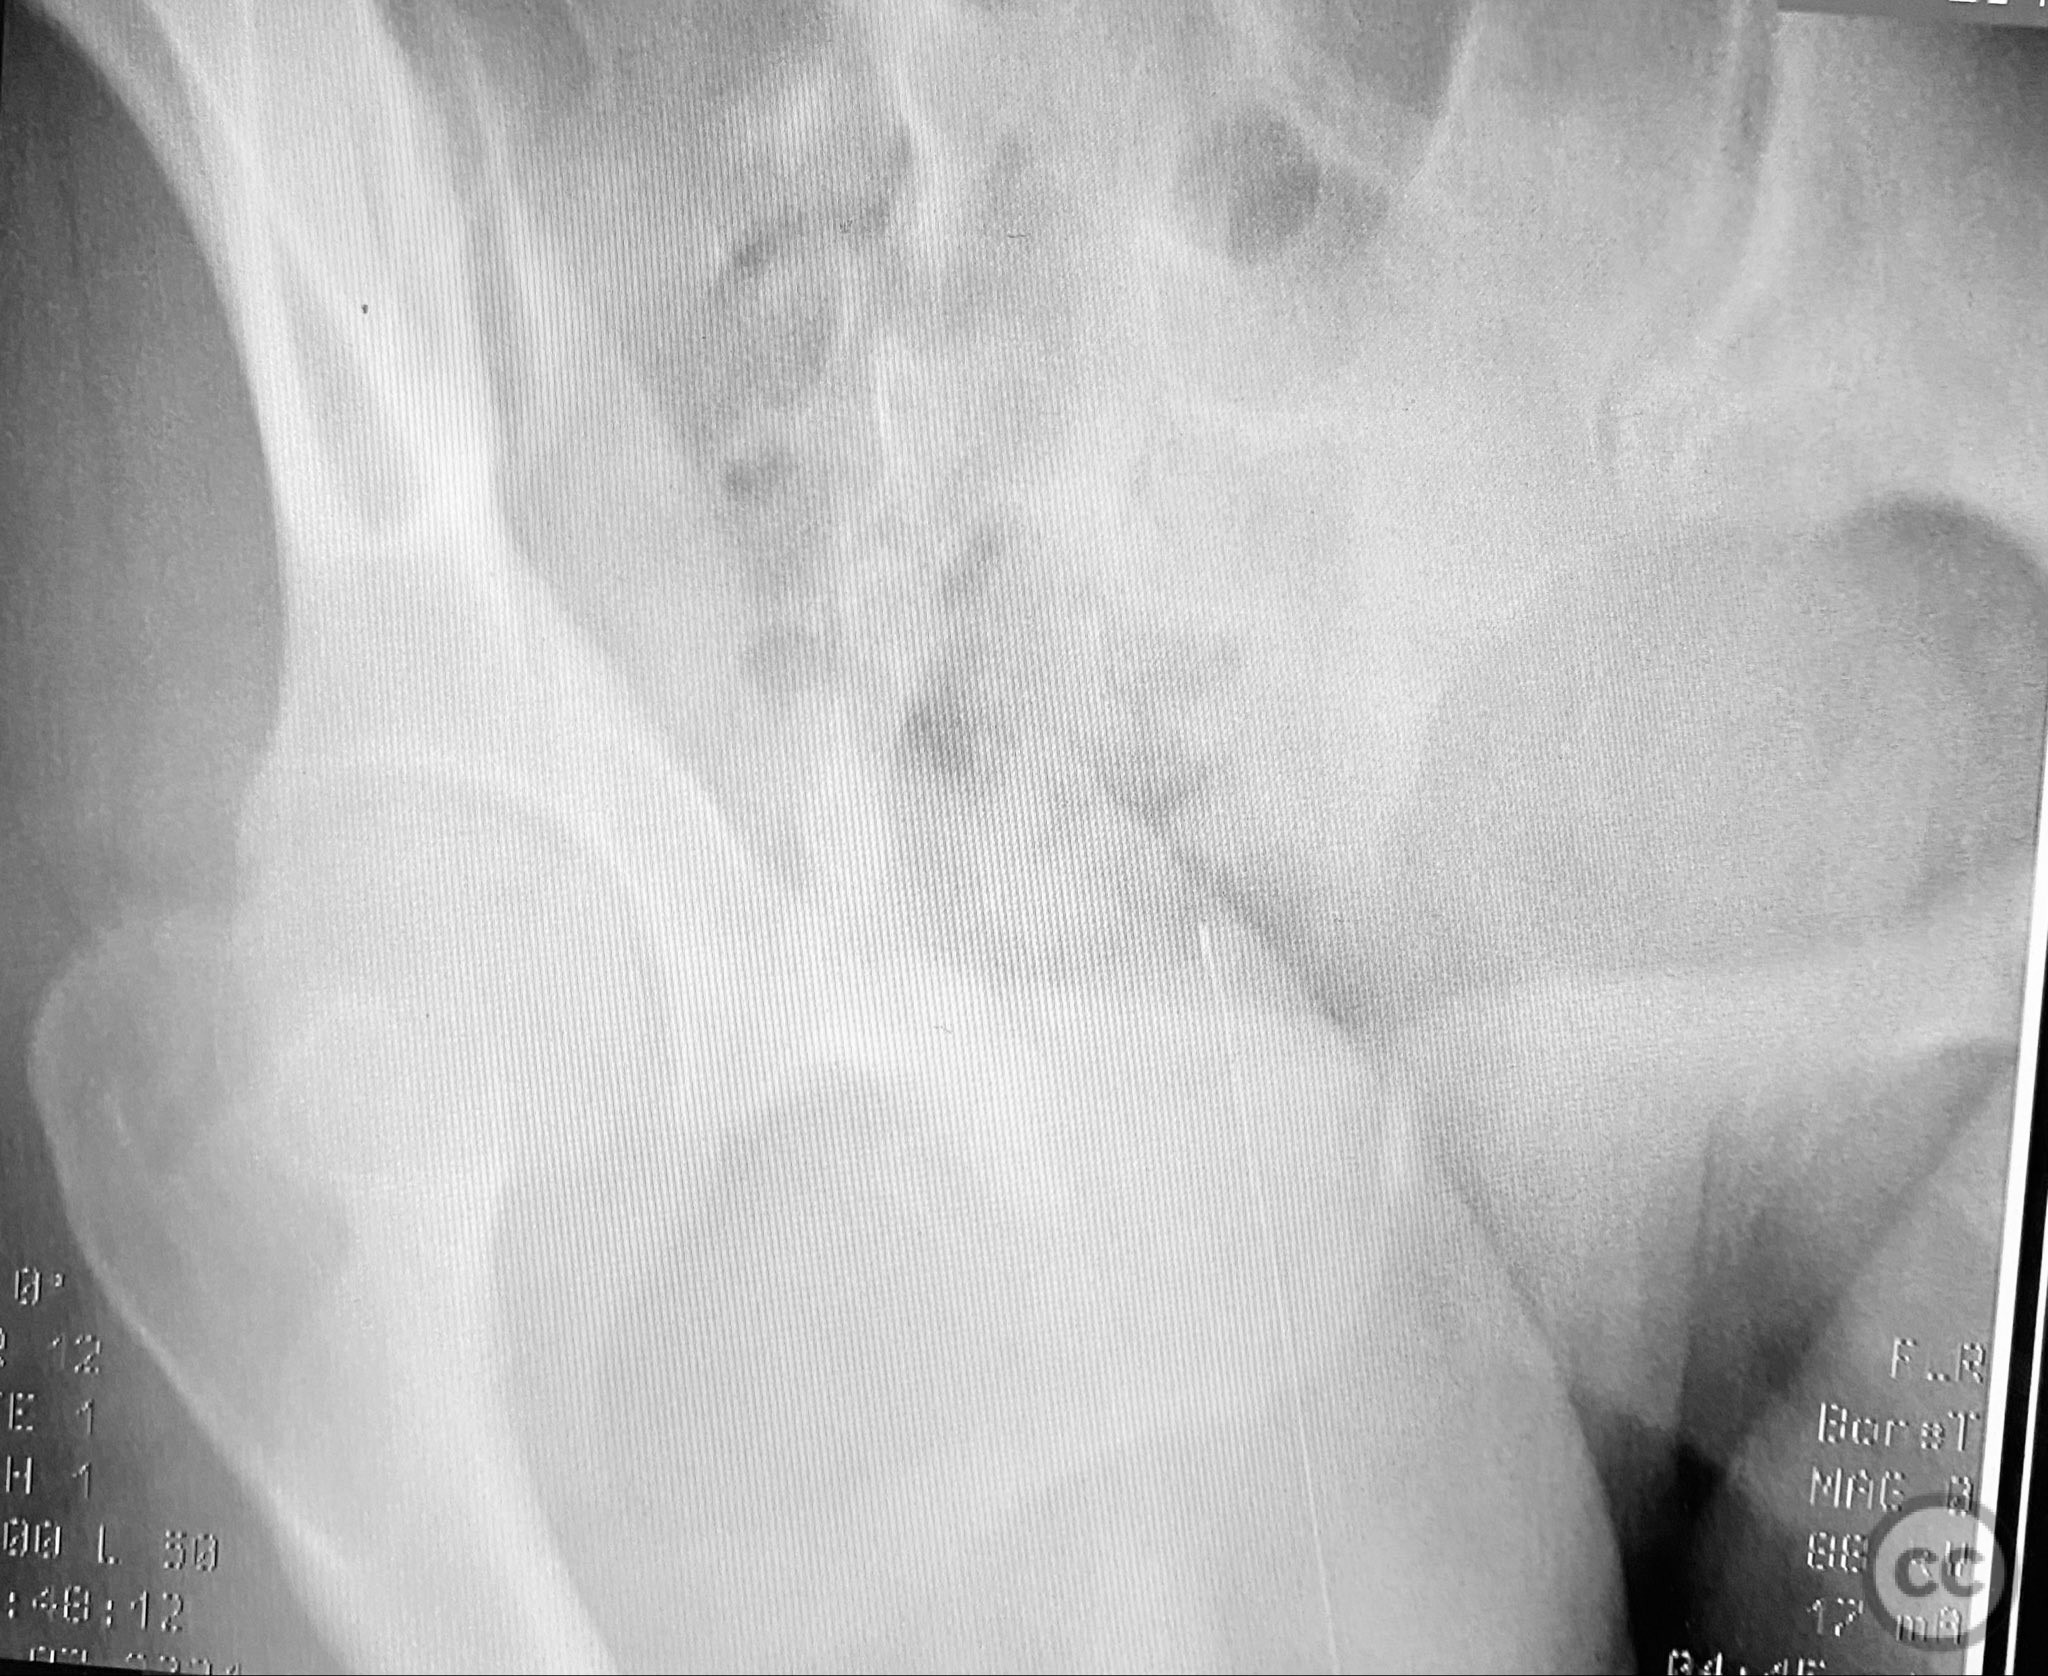

Clinical and radiological findings:  A young adult female sustained a high-energy pelvic injury following a motorcycle crash. She was hemodynamically stable on presentation, with normal neurovascular examination and no evidence of genitourinary, vaginal, or rectal injury. She reported pain localized to both anterior and posterior pelvic regions. Initial plain radiographs (with and without pelvic binder) demonstrated multiple anterior ring fractures and dislocations. The binder images obscured the full extent of injury. Further intraoperative fluoroscopic imaging (AP, inlet, and with lower extremities in "lotus" position) revealed bilateral sacroiliac (SI) joint disruptions (right greater than left), bilateral superior/inferior pubic ramus fractures (right greater than left), and symphyseal diastasis. Notably, the right pubic ramus demonstrated excessive curvature, complicating potential percutaneous screw fixation. AO/OTA classification: 61-C1.3 (bilateral complete disruption of the posterior arch with associated anterior ring injury). Young-Burgess classification: APC III.

Intraoperative fluoroscopy with AP and inlet views, as well as dynamic positioning of the lower extremities, was critical in fully delineating the extent of injury, which had been underestimated on preoperative imaging due to binder application. The excessively curved morphology of the right pubic ramus precluded safe or effective straight screw fixation; therefore, ORIF with a contoured plate was performed using intrapelvic exposure for optimal fit and stability. Indirect closed reduction of the SI joints was accepted, followed by percutaneous trans-sacral screw fixation under fluoroscopic guidance. This case highlights the necessity of thorough intraoperative assessment for occult or underestimated injury patterns in complex pelvic trauma, particularly when initial imaging is performed with a pelvic binder in situ.